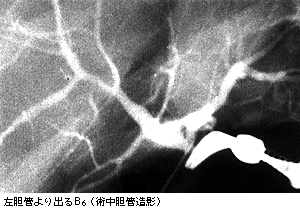

1993年,Couinaudが私の手術を見て「左胆管からB6が出る場合があるので注意が必要だ」と忠告をくれたが,「幸い今まで出くわしていない」との話で終わり,「Fig28を頼りにしている」とつけ加えた。ところが,遂に第119例目にこれにぶつかった。通常の剥離の場所と方法では左門脈枝が露出しにくく,前方の厚いGlisson鞘が邪魔をしているので,術中胆管造影を行なってみると下の写真のような所見を得た。少し肝臓寄りの肝実質を分けることにより,容易に分離が可能となり,事なきを得た。この本のおかげである。